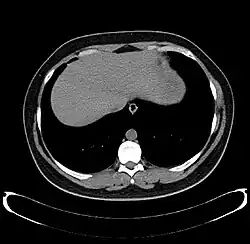

-

Axial CT image showing anomalous hepatic veins coursing on the liver's subcapsular anterior surface[74] -

Maximum intensity projection (MIP) CT image as viewed anteriorly showing the anomalous hepatic veins coursing on the anterior surface of the liver -

Lateral MIP view in the same patient as previous image -